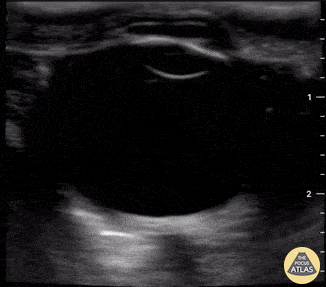

A patient presented with spontaneous intracranial hemorrhage (ICH) secondary to arteriovenous malformation (AVM). She reported severe HA for 3 days with progressive somnolence and associated vomiting. Assessment of her ONSD revealed a width just >5 mm, consistent with an elevated intracranial pressure (ICP). Tessa W. Damm, DO. Intensivist. Milwaukee, WI @DrDamm